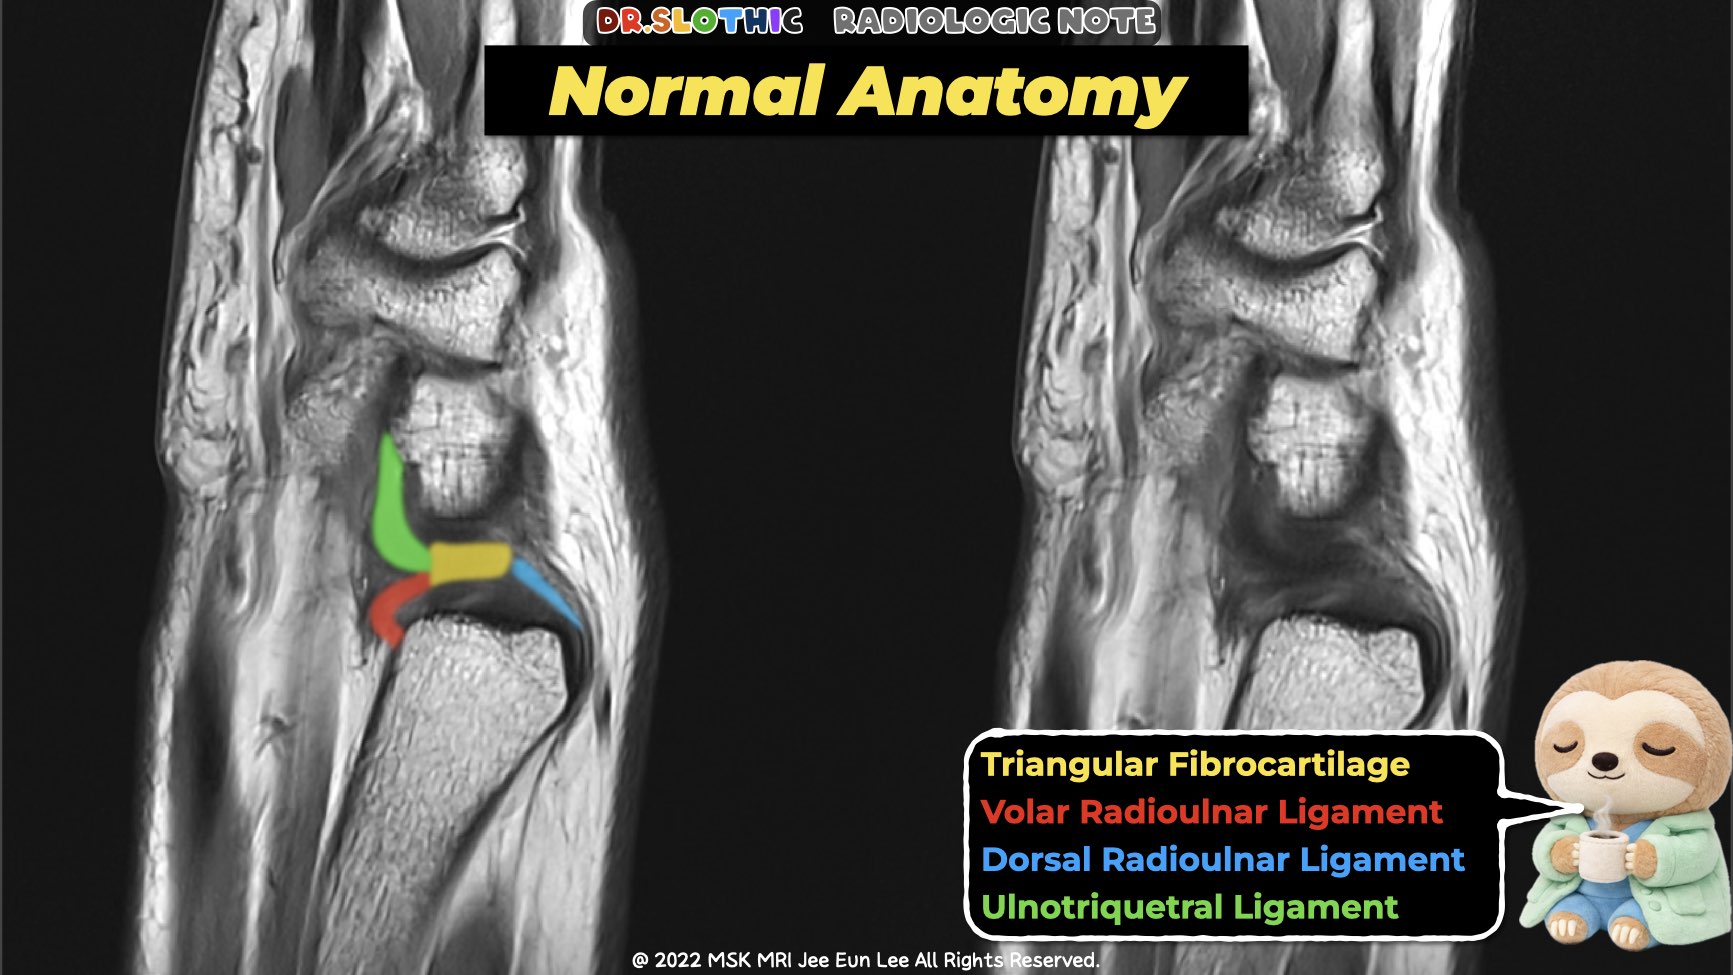

On sagittal wrist magnetic resonance imaging,

the triangular fibrocartilage complex should not be read as a single disc.

It represents a continuous ulnar-sided stabilizing system connecting the distal radioulnar joint to the ulnocarpal joint.

Central Anchor — Articular Disc

- The articular disc lies at the center of the triangular fibrocartilage complex.

- Its dorsal and volar margins are not free edges.

- They blend directly into the dorsal and volar radioulnar ligaments, forming the core stabilizing arms.

Radioulnar Ligaments

Dorsal Radioulnar Ligament

- Thickened dorsal peripheral margin of the articular disc.

- Extends from the dorsal rim of the distal radius (sigmoid notch)

to the ulnar styloid and fovea of the ulnar head. - Consists of:

- Becomes taut in pronation and provides dorsal stability of the distal radioulnar joint.

- Blends dorsally with the floor of the extensor carpi ulnaris tendon sheath.

Volar Radioulnar Ligament

- Thickened volar peripheral margin of the articular disc.

- Originates from the palmar rim of the sigmoid notch and lunate facet of the distal radius.

- Also composed of superficial (styloid) and deep (foveal) fibers.

- Tightens in supination, acting as the primary volar stabilizer of the distal radioulnar joint.

- Serves as the proximal origin for the major palmar ulnocarpal ligaments.

MRI Take-Home Message

On sagittal wrist magnetic resonance imaging:

disc → radioulnar ligaments → ulnocarpal ligaments

should be followed as one continuous stabilizing chain.

Instability rarely comes from the disc alone.